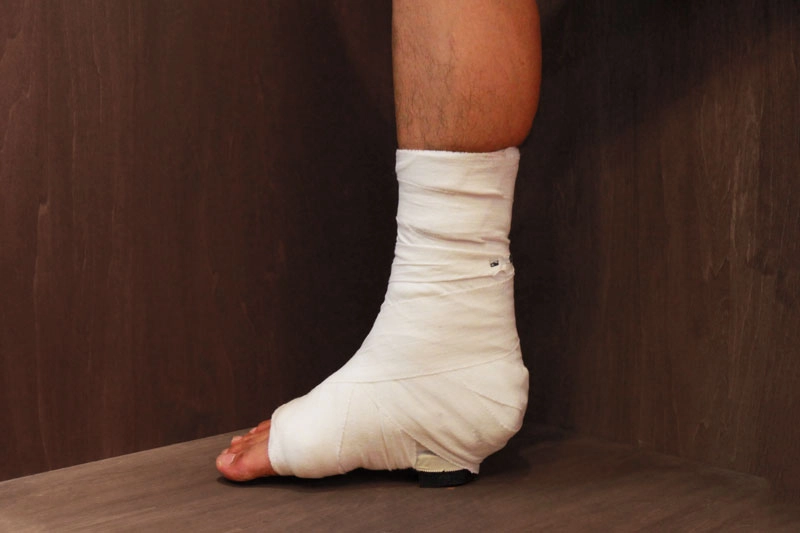

① ギプス固定(保存療法)

手術とは異なり、傷跡を作らずにアキレス腱の修復ができます。

ギプスの工夫により、関節の硬さを最小にしながら、アキレス腱を回復させます。 -

初診の固定

アキレス腱を太く回復させるために、断裂部を近づけて、つま先を下げた固定。ここで無理して90度で固定するとアキレス腱が細くなり、再断裂の危険が増える。

2週間後の固定

断裂部がくっついて安定してくる時期。リハビリで可動域を広げやすくするため、足首を90度に近づけて、つま先を上げて固定。固定していると癒着が進行するので、ここで角度を90°に近づける。

4週間後の固定

断裂部がさらに安定してくる時期。アキレス腱が伸びる足首90°で固定し、歩きやすくする。4週後からリハビリが開始し、早期に可動域を出す。

Step1. 保存療法

断裂したアキレス腱を再生させるために足首を固定します。

アキレス腱は回復力のある組織なので、完全断裂でも心配はいりません。ギプスを工夫し、関節の硬さを少なくします。

アキレス腱再生のために固定 1日目

患部を安静にしアキレス腱の再生を促すために、ギプス固定を行います。

その際、足首の角度はつまさきを最大限伸ばした状態(最大底屈位)にしてアキレス腱を元の長さと同じように治すようにします。

完全断裂か部分断裂かどうかで固定する範囲、強度を変えます。

できる限り小さい固定にし、日常生活を制限しないようにします。